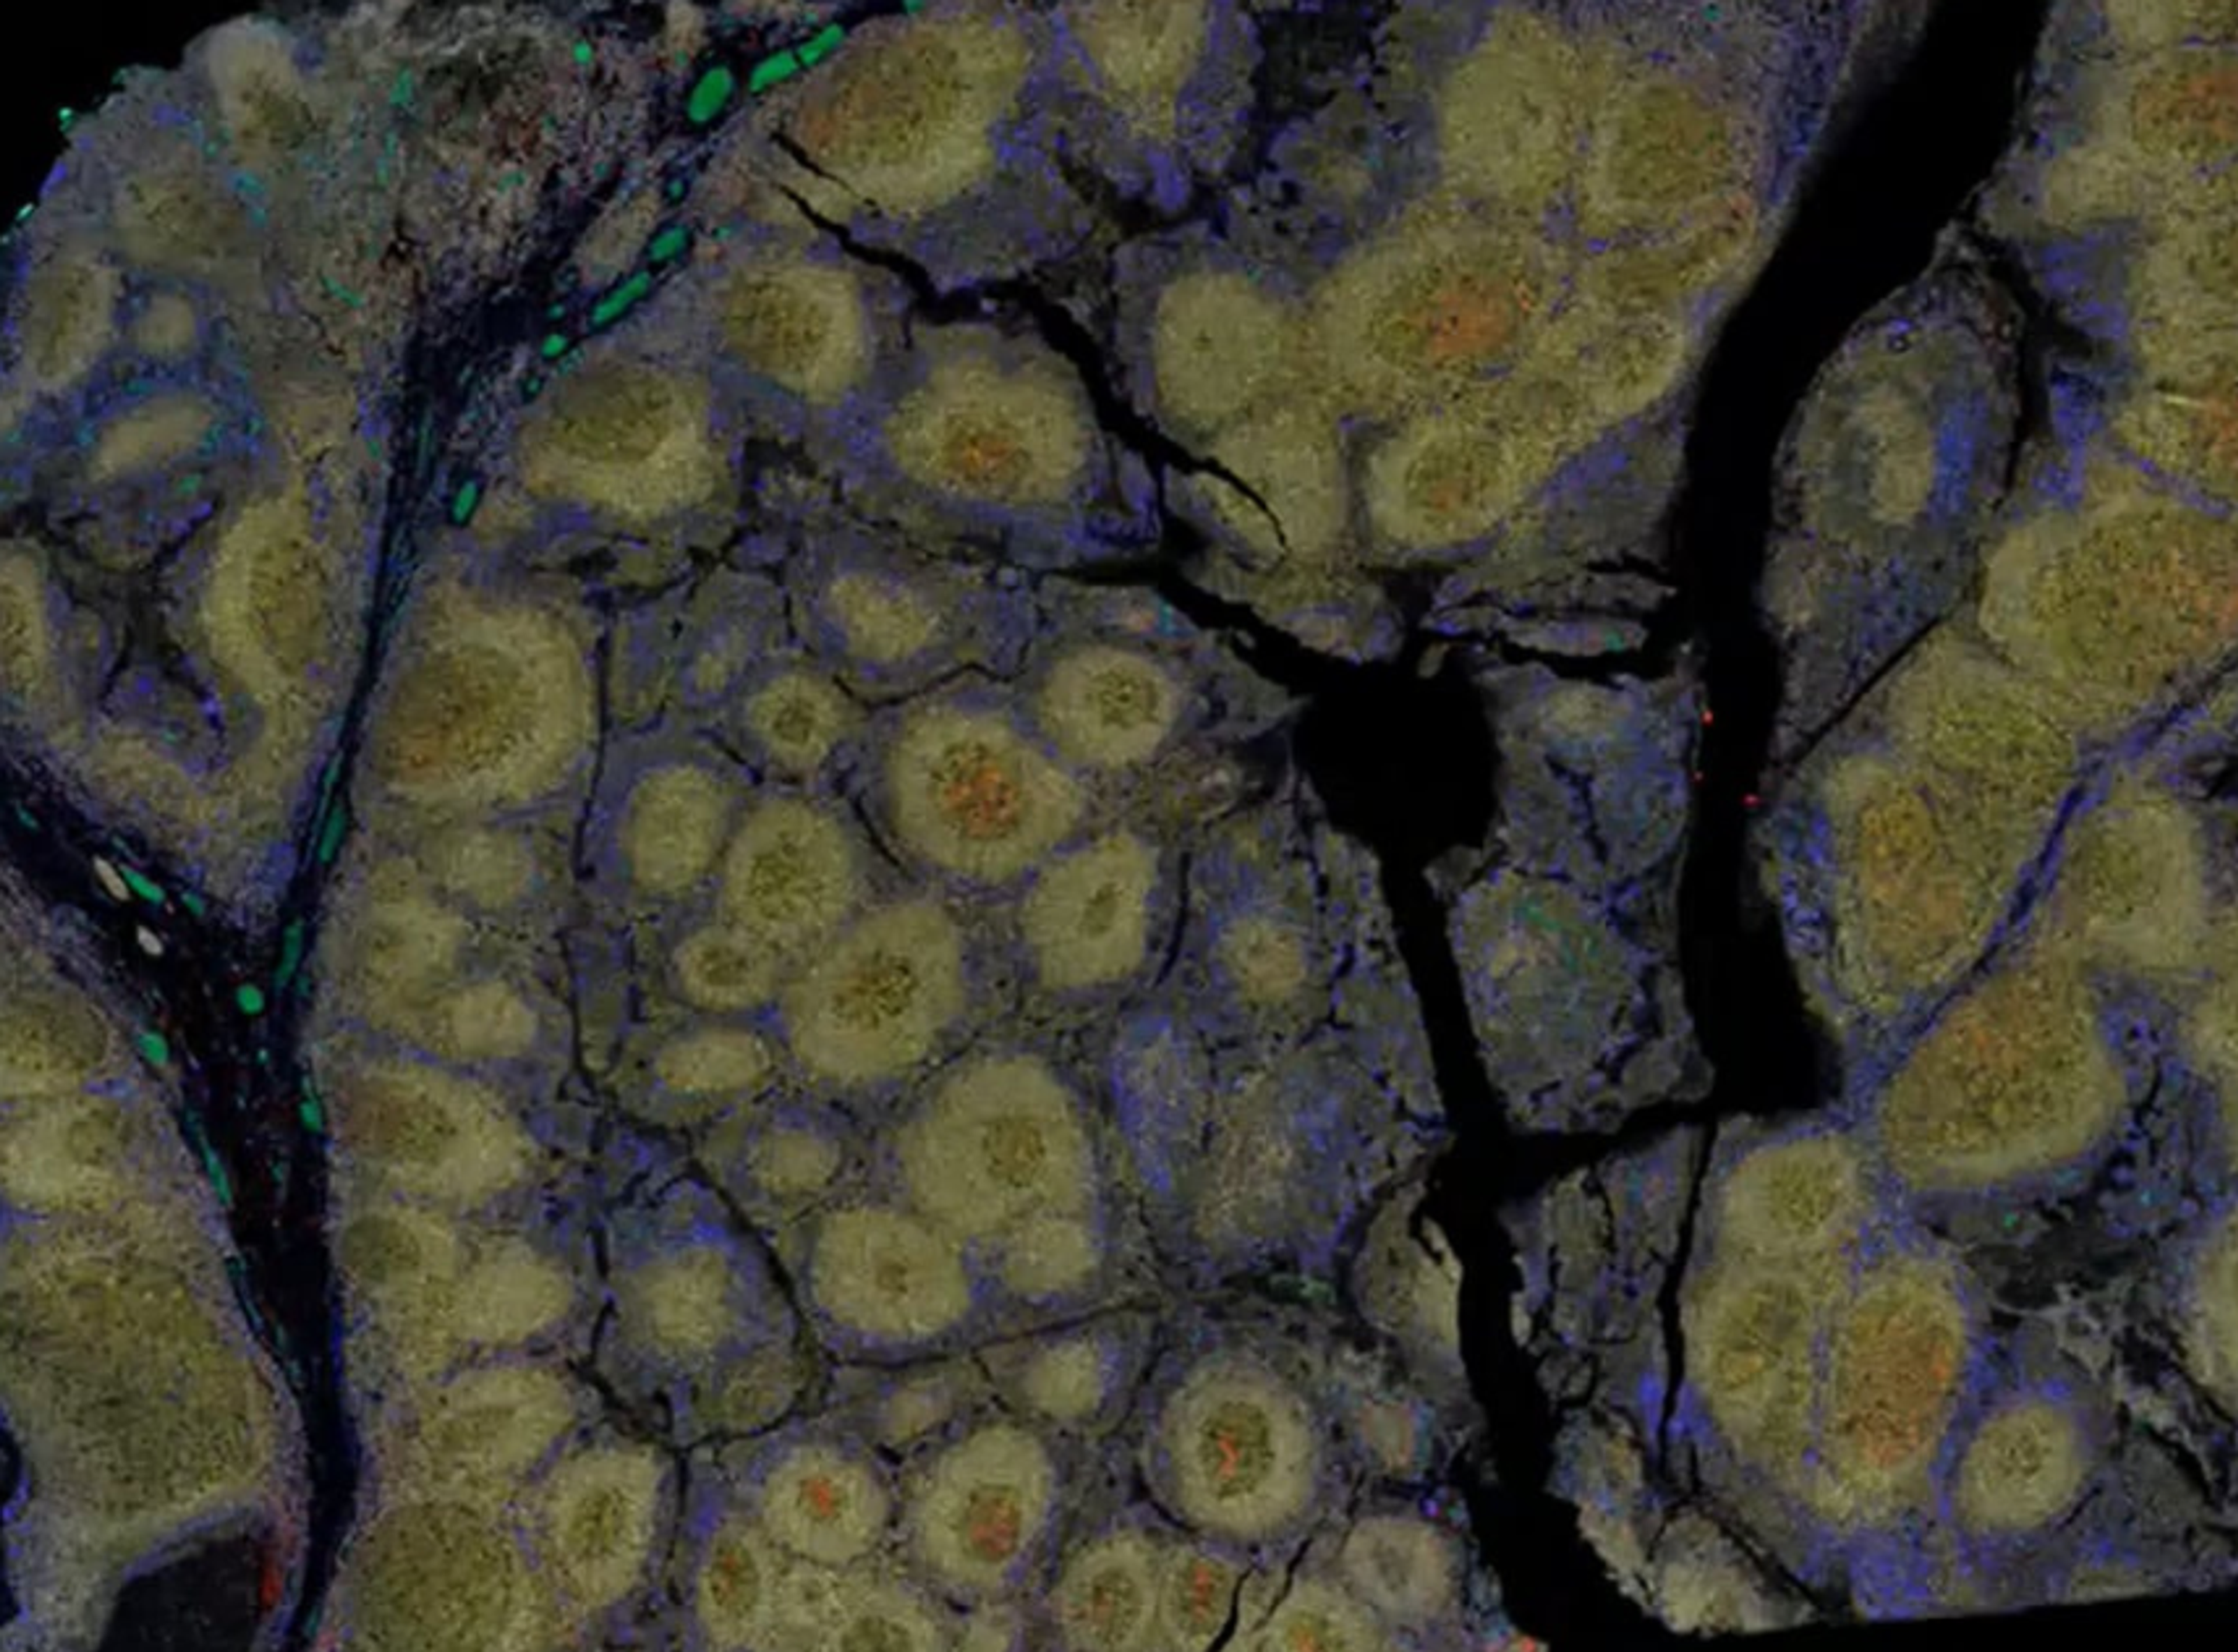

Dr. Sarah McArdle presents on open source software for quantitative image analysis, focusing on multiplex staining for high dimensional analysis. She explains the RareCyte Orion microscope and its image acquisition process. The discussion covers the advantages of open source software, challenges in analyzing large datasets, and the importance of validating staining quality.